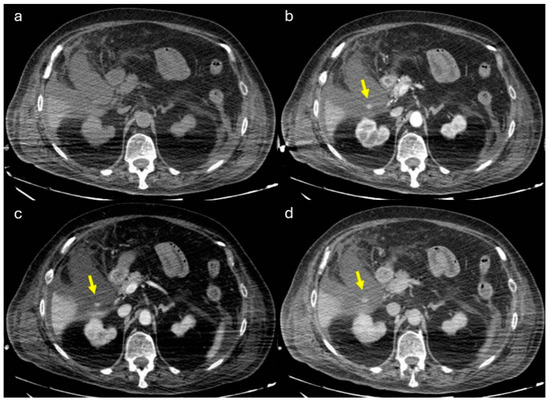

2. Imaging

3.1.3. Imaging and Diagnostic Findings